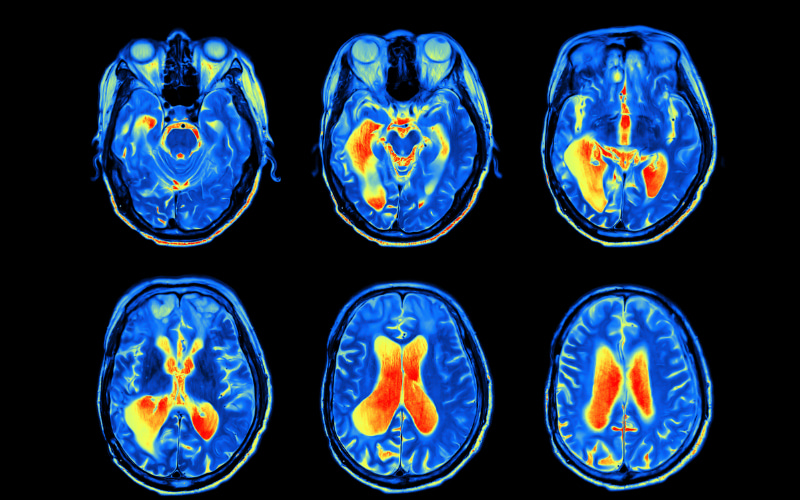

The field of Neuroscience is ever-diversifying and developing, with many of the cellular mechanisms and biochemical processes that interact within the brain remaining misunderstood. With both an ageing population and an increase in the prominence of inflammatory diseases, such as hay fever, allergies and asthma, it is important that we begin to focus our research on the rising epidemic of excessive inflammatory responses.

This project seeks to utilise newly discovered drugs and technologies, that have been shown to reduce microglia inflammation, to understand what specific influence they have on the biochemical and cellular mechanisms on microglia cells, which are important cells in the maintenance of the brain's neurons and synapses. Through this, the interplay between microglial inflammation and neurodegeneration may be explored, bringing us closer to alleviating the impacts of Alzheimer's disease.